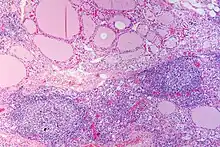

En microscopie les lésions consistent en une association de fibrose interstitielle, d'infiltration lymphoïde et de destruction épithéliale[1],[2]. Le degré de fibrose est très variable[1]. L'infiltration lymphoïde présente une organisation en follicules avec des lymphocytes B au centre et des lymphocytes T dans le cortex[2]. Les cellules épithéliales thyroïdiennes sont également modifiées, apparaissant élargies et acidophiles (cellules de Hürthle)[2].